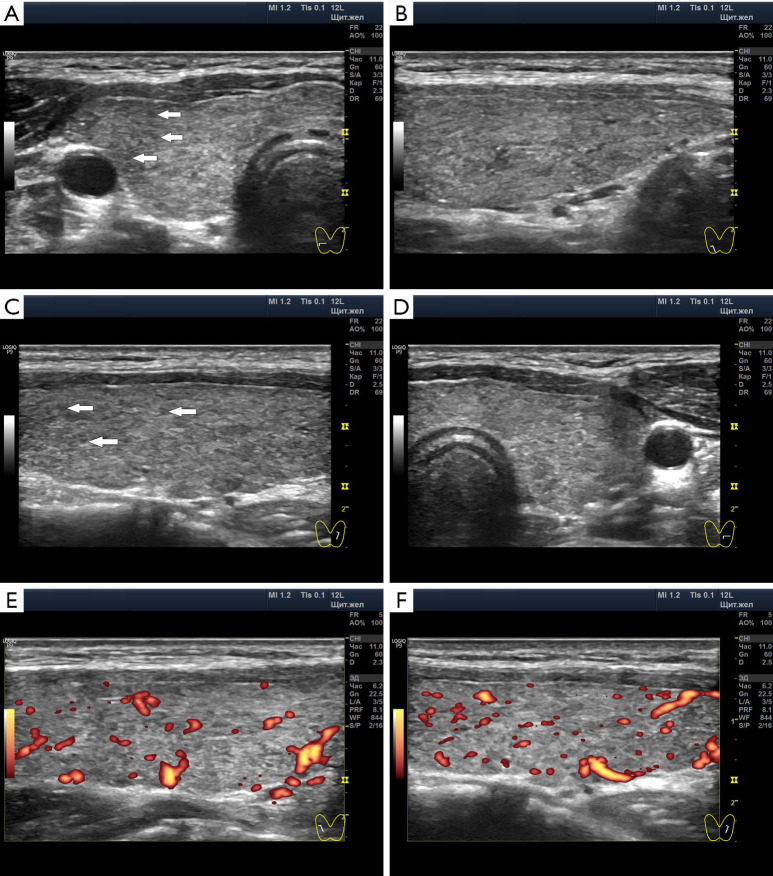

Case description: A 15-year-old female patient experienced a transition from SCH to euthyroidism against the background of highly normal values of thyroid hormones, the full state of the thyroid parenchyma and significantly increased blood flow in the Doppler mode. She did not take medications. Conditions likely to trigger SCH included acute respiratory illness, living in a cold climate, and mental stress due to prolonged preparation for exams. The transition to euthyroidism occurred after sufficient stay in the conditions of a southern resort in the summer and mental comfort.

Conclusions: As a result, it was revealed that the amount of thyroid-stimulating hormone (TSH) depends on the intensity of energy expenditure of the body in accordance with living conditions. The increased intensity of blood flow in the thyroid during SCH and euthyroidism shows the leading role of the autonomic nervous system and the auxiliary importance of TSH. The concentration of thyroid hormones at the maximum limit of normal in SCH, together with the significantly increased Doppler blood flow, suggests common elements of pathogenesis with Graves' disease through the autonomic nervous system. With many months of thyroid overstrain, ultrasound shows signs of corresponding depletion in the form of hypoechogenicity of the lobules, but the preservation of a sufficient amount of hormone-producing tissue.